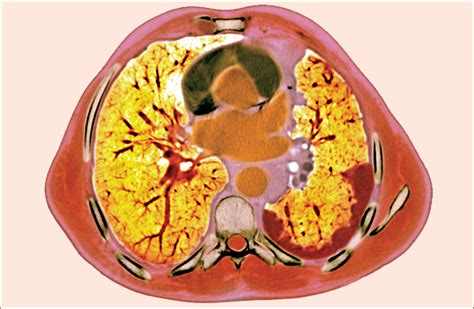

• Imaging tests: X-rays, CT scans, MRI, and PET scans can help locate the tumor and determine its size and extent.